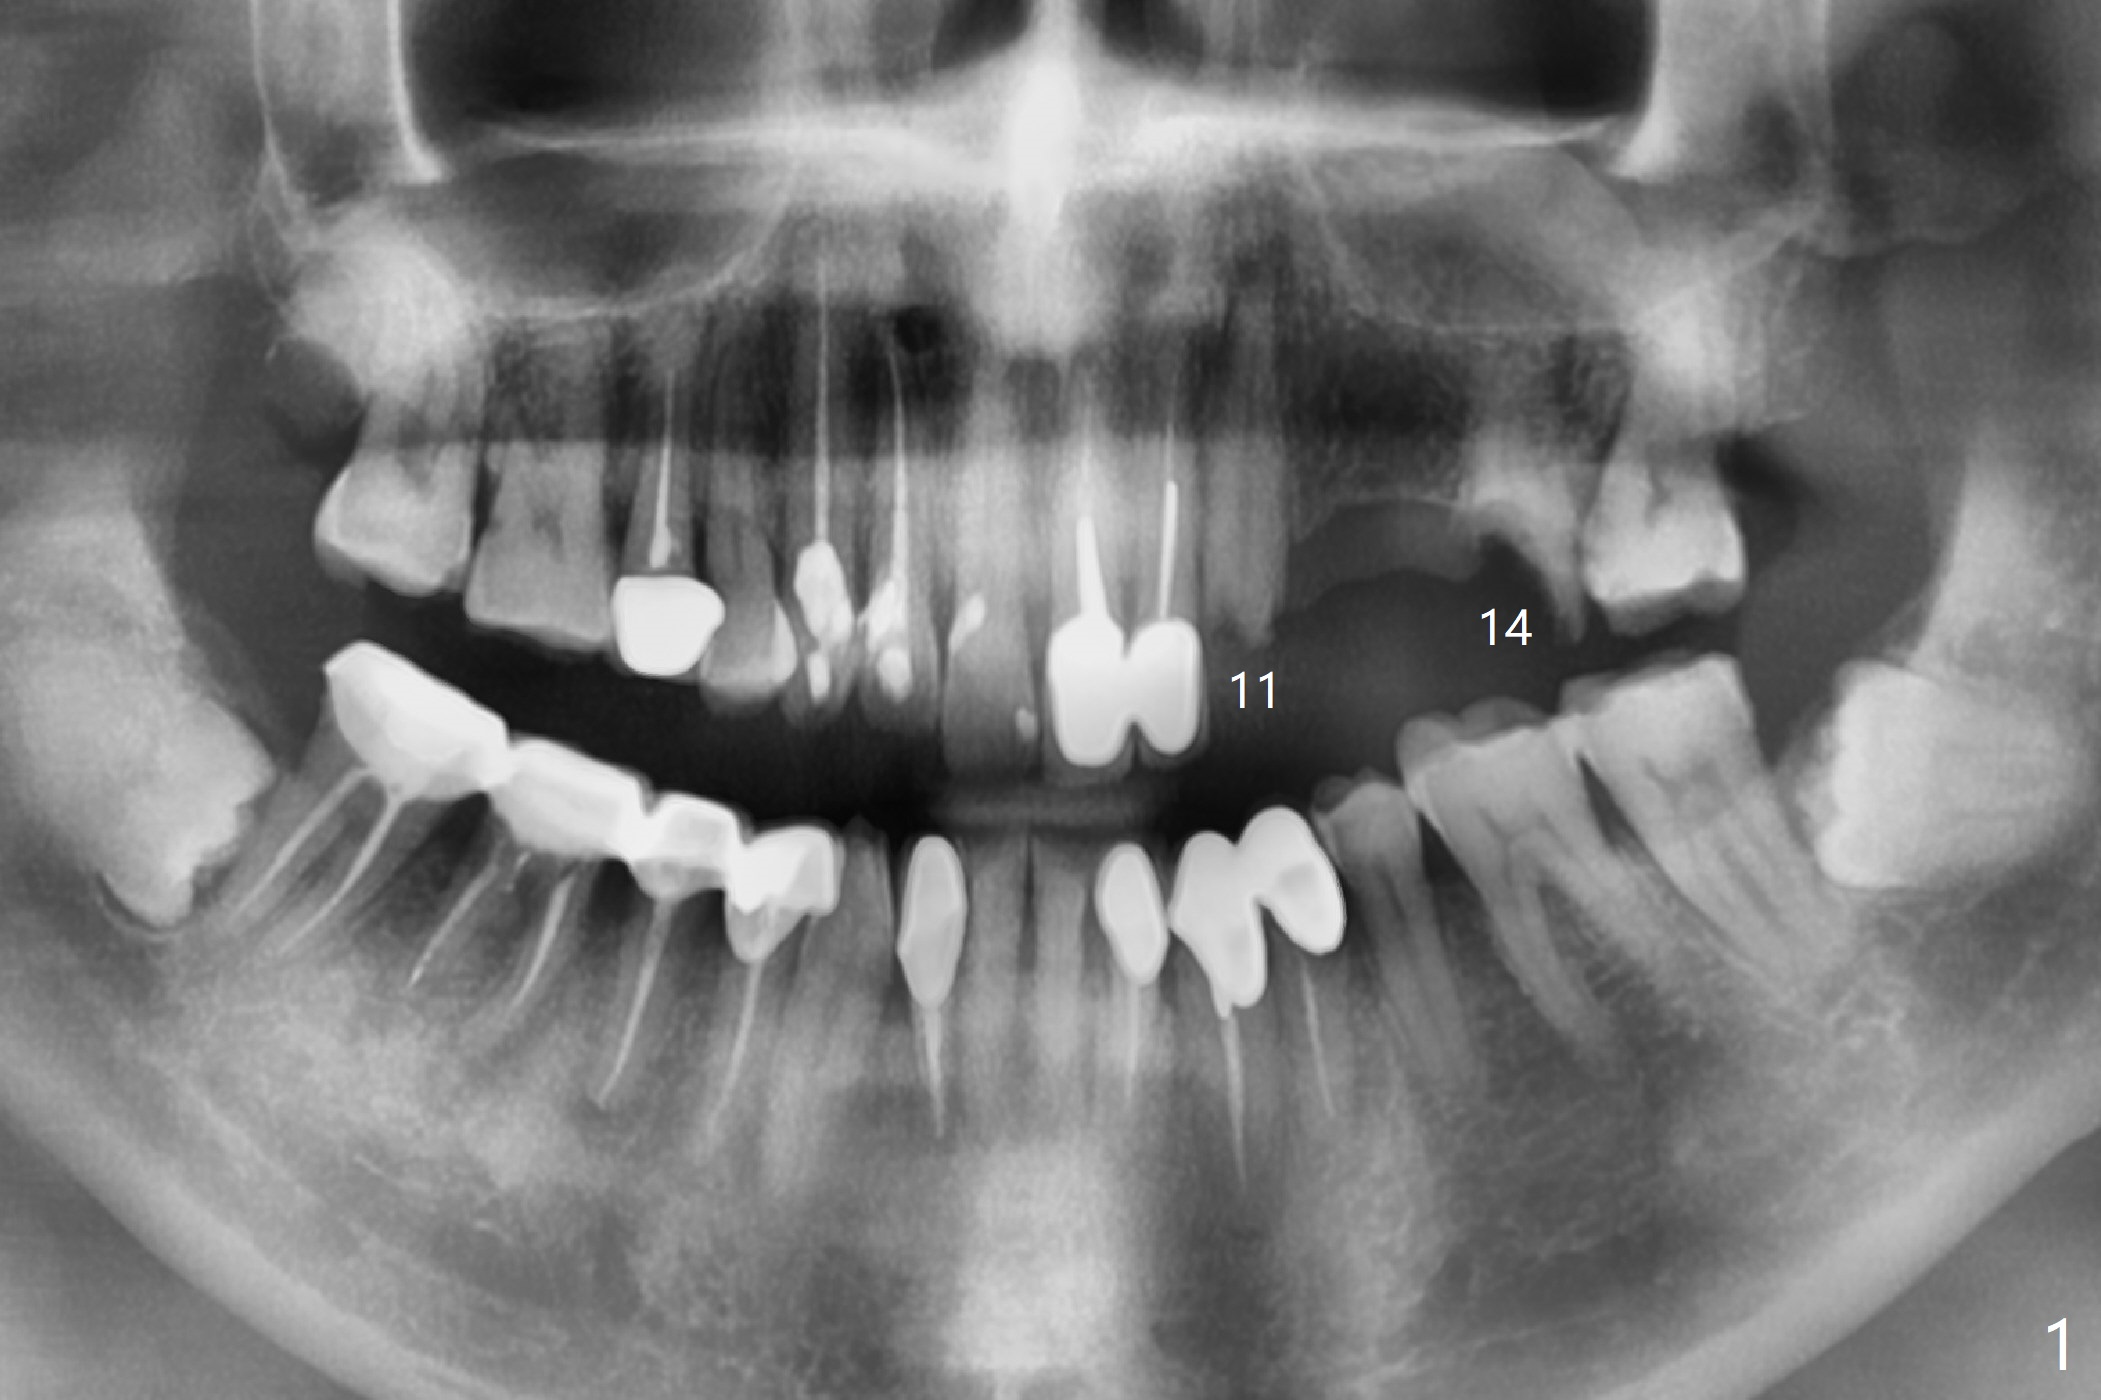

A 77-year-old man has multiple restoration with long roots (suggesting bruxism, Fig.1). The #11-14 FPD dislodges. Twenty days postop, he will travel to his home country and stays for 2 months. Four months postop, he will leave again. To strengthen provisional FPD stability and early final restoration, each implant will be placed at each edentulous area. The longest bone-level implant will be placed at #11 with bone height >20 mm (Fig.2). Since the bone width (buccopalatal) is 4 mm at #12, a 2x14(2) mm 1-piece implant is to be inserted (Fig.3); while a 3.8x10 mm 2-piece one at #13 with underprep because of low density. As the septal bone height is limited at #14 (Fig.4), a 5x8.5 mm implant is going to be placed.